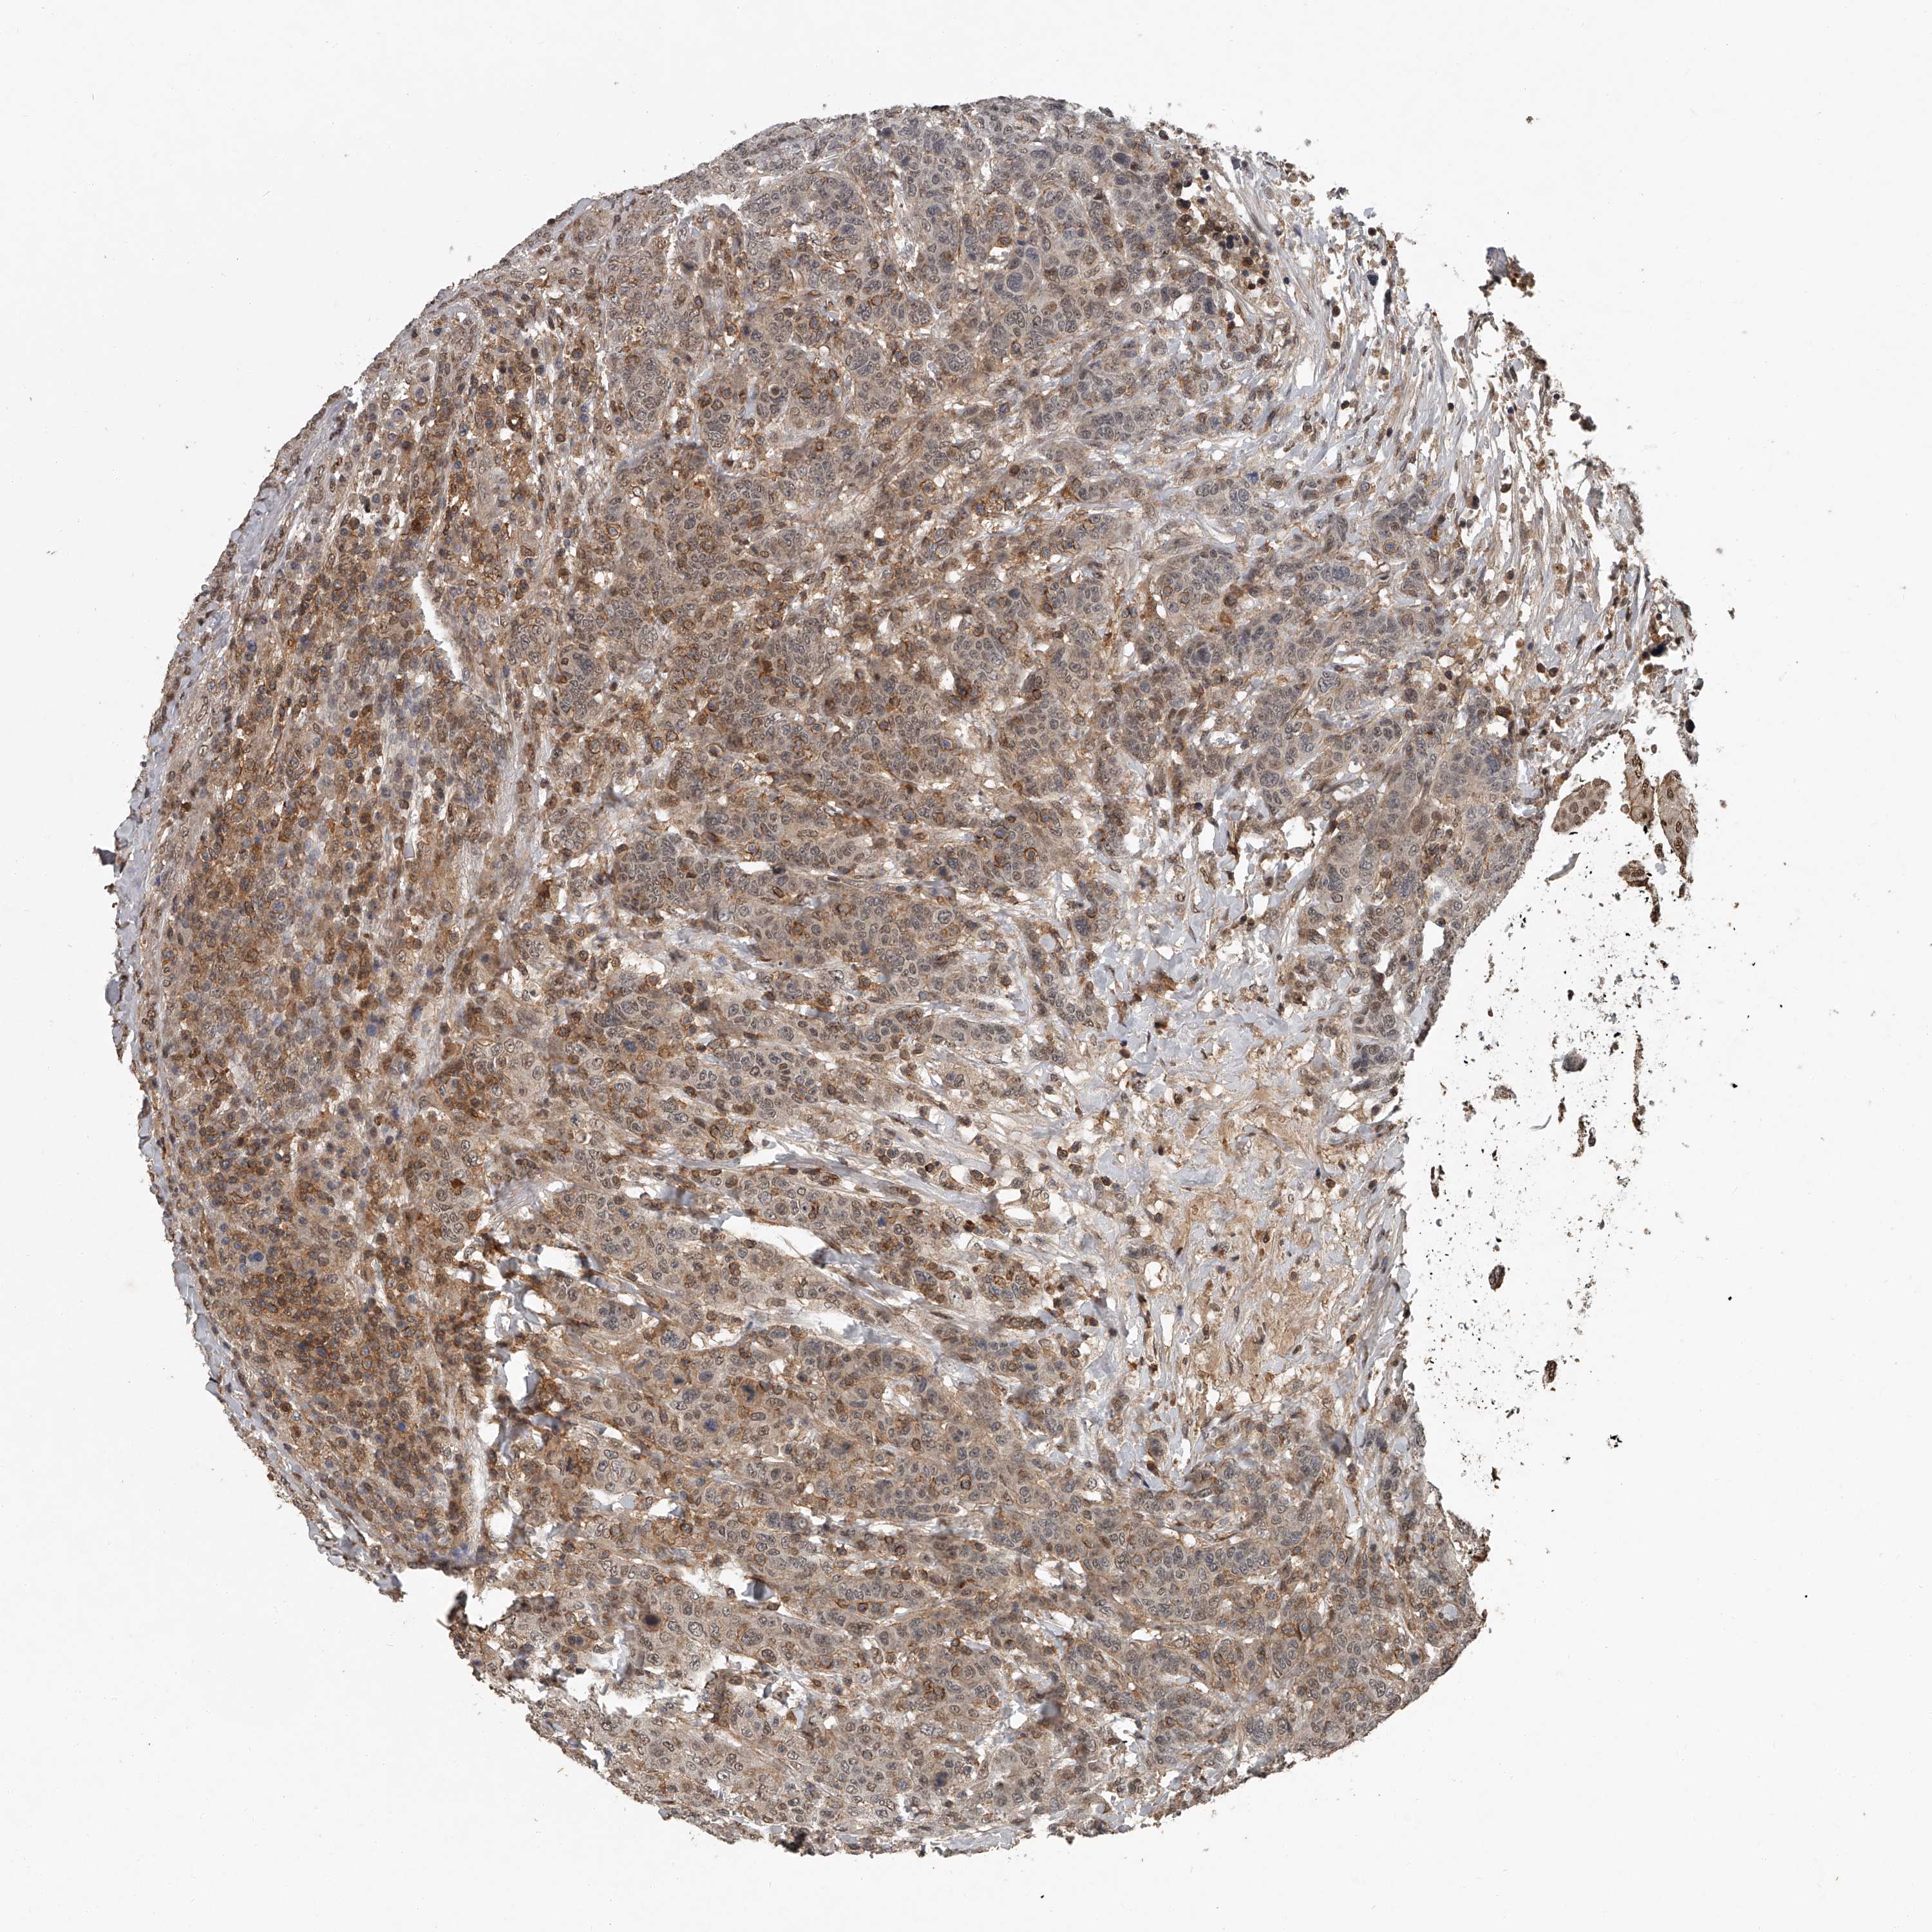

BRCA TCGA BRCA VALIDATION PROTEIN EXPRESSION